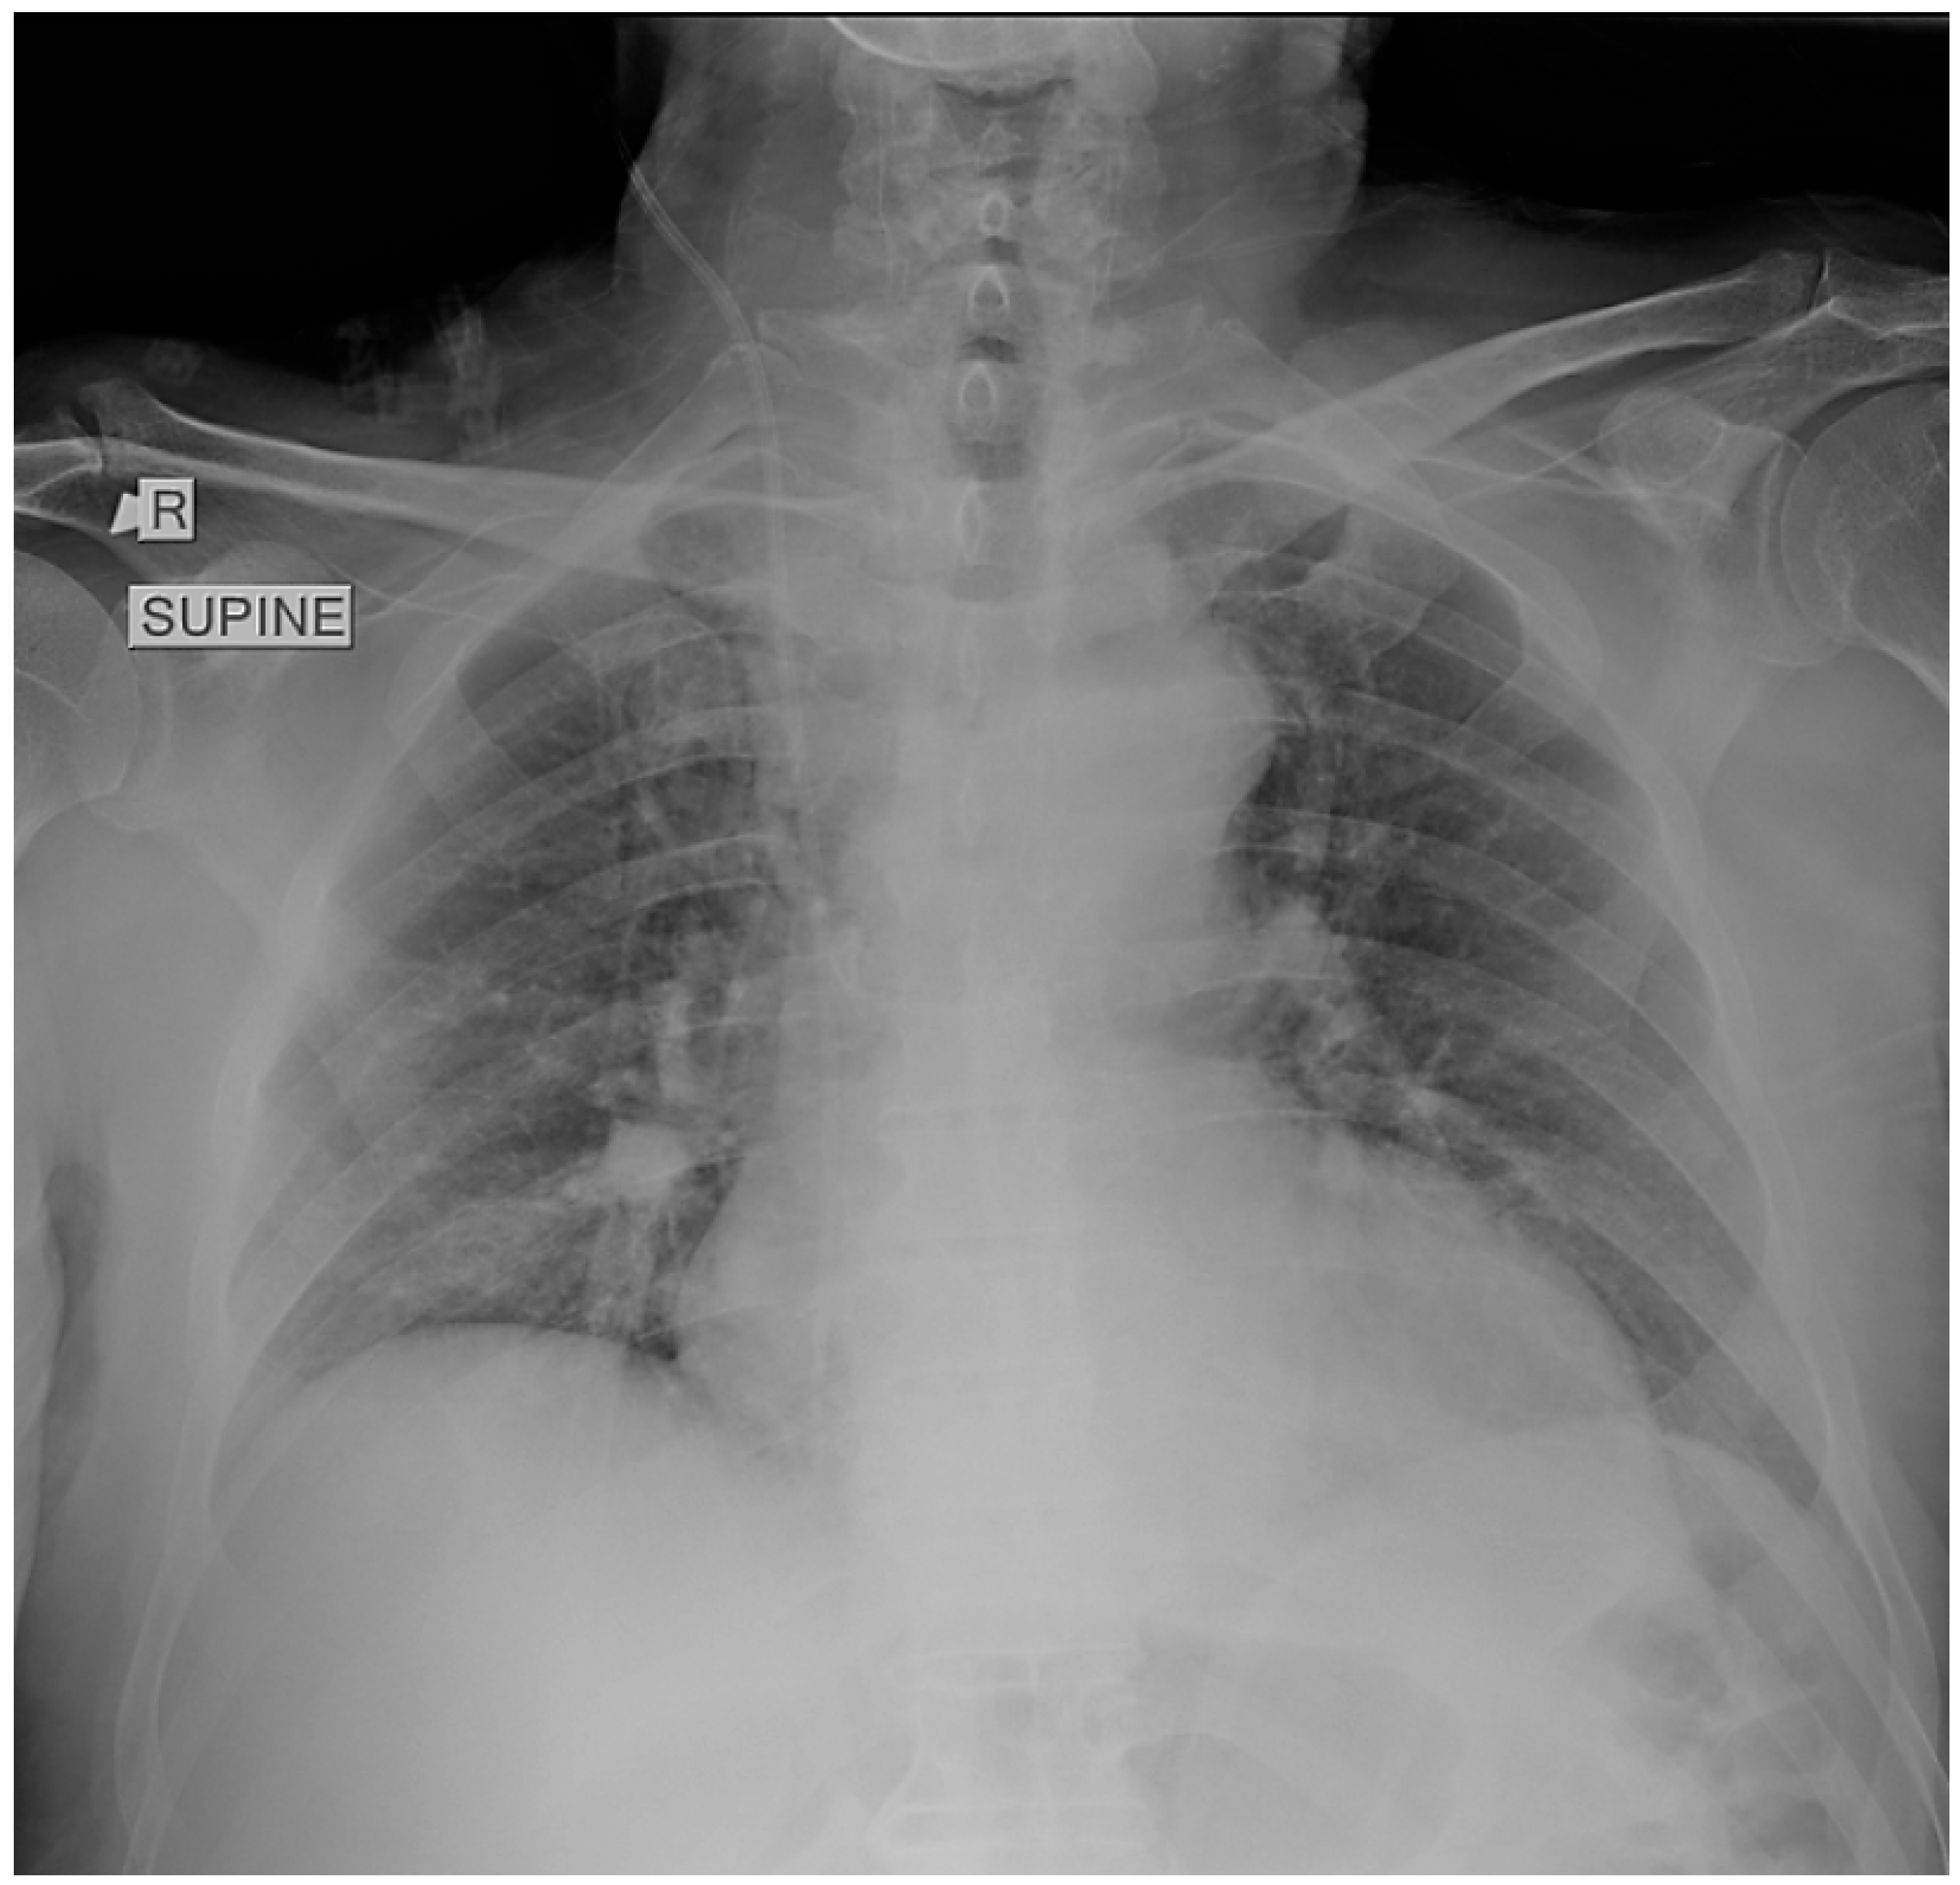

A supine chest radiograph demonstrated normal cardiac size and clear lung fields, without focal consolidation, pleural effusion, or pneumothorax (Figure 1).

No abnormalities were identified that could explain the profound hypoxemia. Electrocardiography revealed sinus tachycardia with an S1Q3T3 pattern and incomplete right bundle-branch block, consistent with right-heart strain.

Figure 1. Supine chest radiograph obtained in the emergency department showing no focal consolidation, pleural effusion, or pneumothorax. The lung fields and costophrenic angles are clear, and cardiac size is within normal limits. No radiographic abnormalities are identified to explain the patient’s profound respiratory distress.